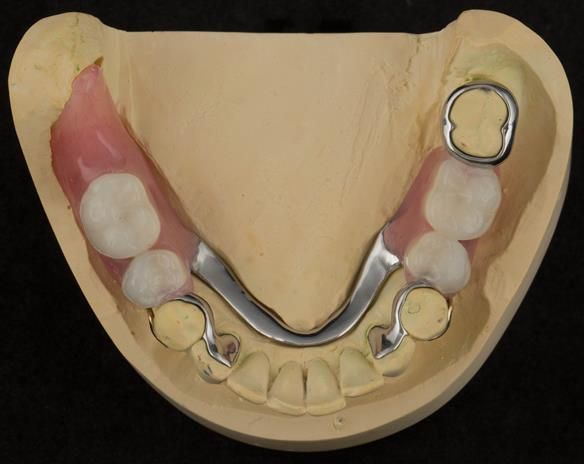

This newsletter describes in step by step detail Angela's transition through immediate partial dentures to crown supported definitive metal based dentures.

The clinical situation and treatment process is shown in detail below with photographs. I (Finlay Sutton) provided the clinical work and Rowan Garstang provided the technical work.